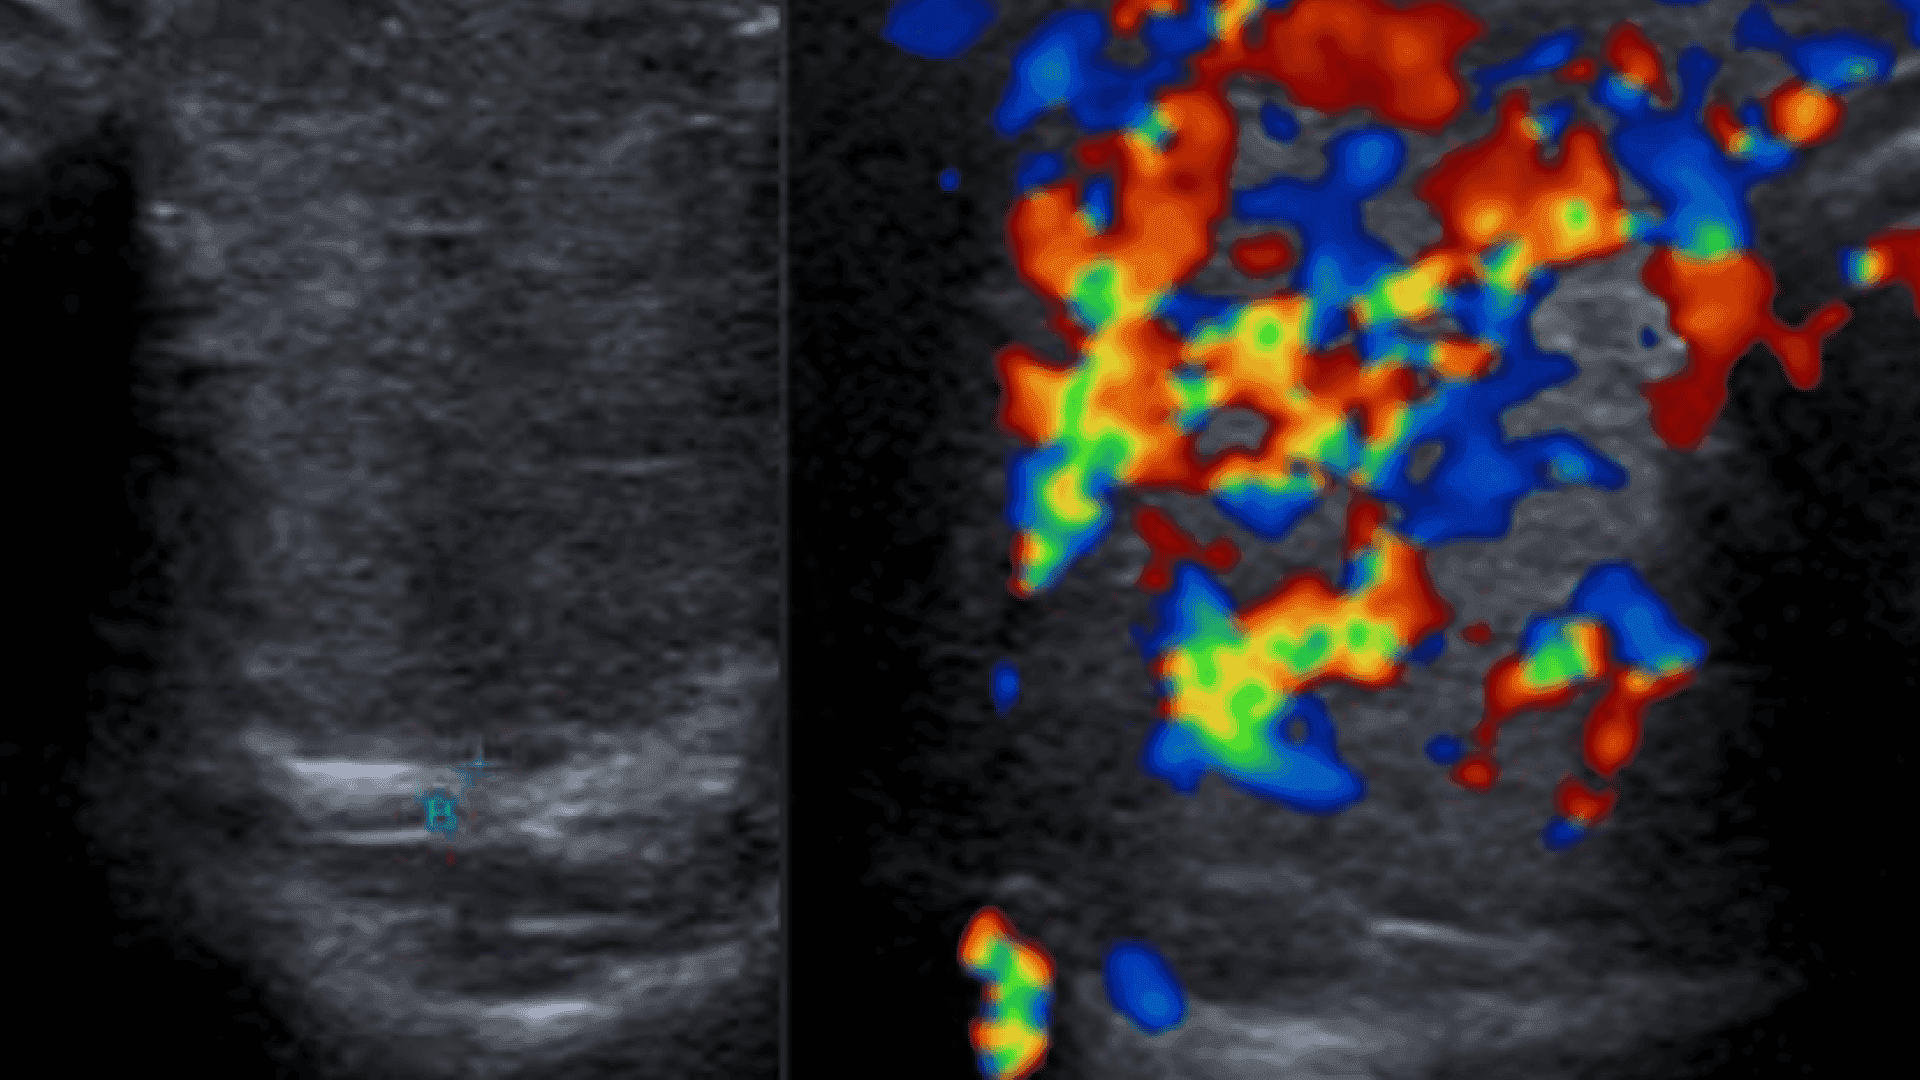

El uso de Doppler color también permite identificar el artefacto twinkling, que incrementa la especificidad para detectar cálculos.

Ultrasonido renal realizado con transductor convexo que demuestra un foco hiperecogénico compatible con litiasis en el sistema colector, asociado a sombra acústica posterior, hallazgo característico de cálculos calcificados. Se observa además dilatación retrógrada del sistema pielocalicial (hidronefrosis), lo que sugiere obstrucción urinaria secundaria. El ultrasonido constituye una modalidad inicial ampliamente utilizada en la evaluación de urolitiasis, particularmente en pacientes pediátricos y embarazadas, permitiendo identificar tanto el cálculo como las repercusiones obstructivas sobre el riñón.